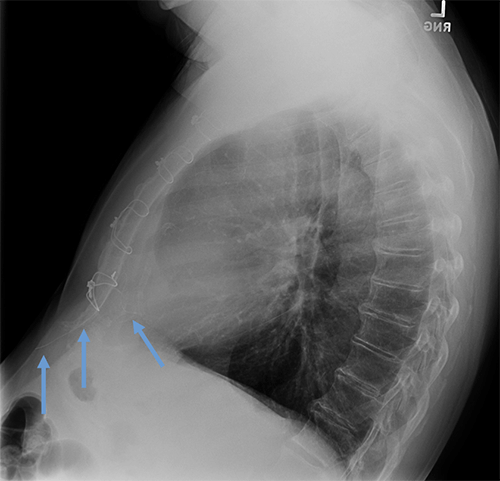

- CEID images with lead types:

Pacemaker with epicardial leads